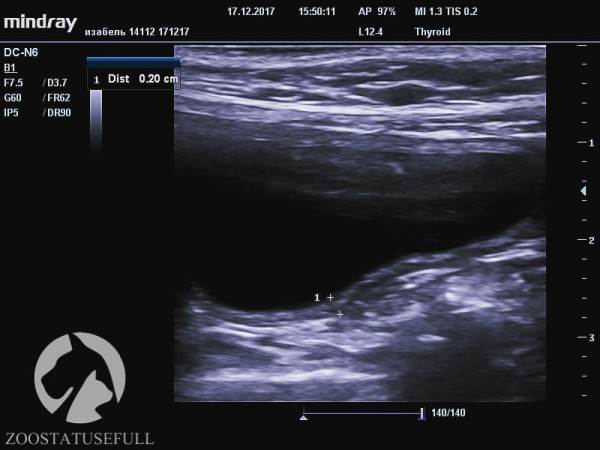

Мочевой пузырь кошки Изабель на УЗИ

На снимках, используемых в этой статье, кошка Изабель — являющаяся показательным примером того, что случится с органами мочевыделительной системы «спинальника», если животному не опорожнять мануально мочевой пузырь. Изабель утратила функцию произвольного мочеиспускания в возрасте котёнка, после чего целый год жила в приюте для бездомных животных, где не знали о необходимости мануально опорожнять мочевой пузырь кошке, которая не может осуществить диурез самостоятельно. За самостоятельное мочеиспускание воспринималось протекание по каплям на фоне переполнения.

Постоянное переполнение и перерастяжение мочевого пузыря превратили когда-то упругий «шарик» (мочевой пузырь) в растянутую атоничную «тряпочку». Качественно мануально опорожнять этот мочевой пузырь сейчас — очень тяжело даже опытным ветеринарным врачам.